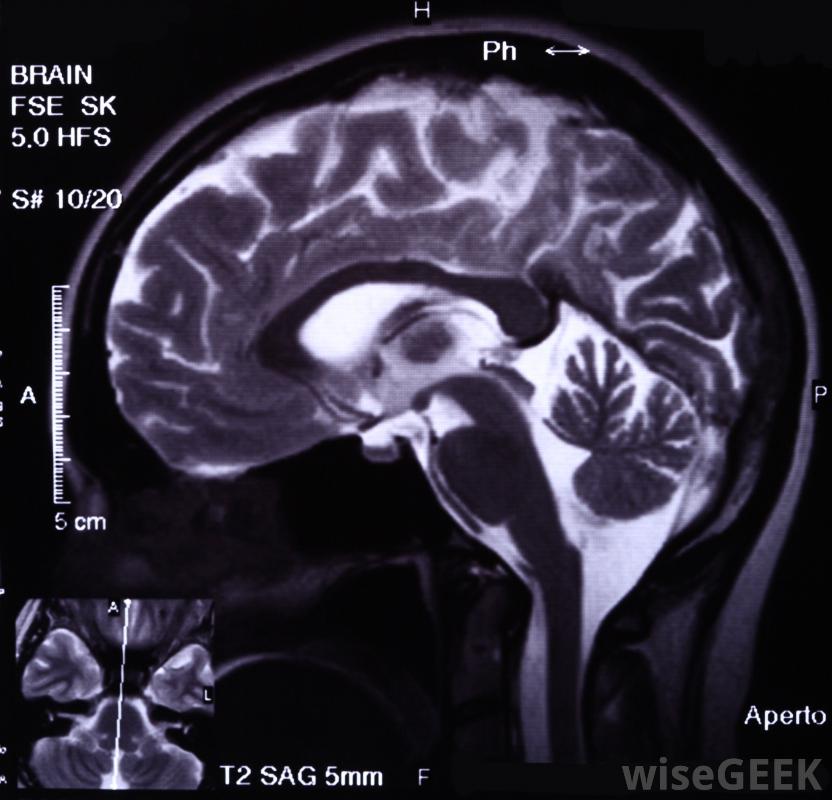

PET扫描图像可与计算机断层扫描(CT)或磁共振成像(MRI)结合,这一过程称为

联合注册或

图像融合。目前大多数PET扫描与CT扫描结合,以生成提供详细信息的图像有关器官和组织的解剖学信息。PET/CT扫描的结果通常比PET扫描结果提供更准确的诊断和治疗信息。PET和PET/CT扫描最常用于帮助诊断和重新分期癌症、评估心肌和检测大脑异常。在所有情况下,都可以解释PET/CT或PET扫描结果可能是一个非常复杂的过程,通常应保留给接受过核医学专业培训的医生和放射科医生。

MRI可以结合使用通过PET扫描得到大脑的精确图像